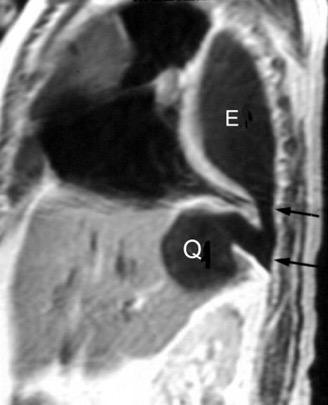

Quiste hidatídico.

Comunica con el hiato esofágico y el espacio pararrenal anterior.

Colecciones “inflamatorias” abdominales llegan al tórax vía el hiato esofágico o por vía transdiafragmática

Afectación transdiafragmática: 5,6-43,7% de quistes hepáticos. “Área desnuda” del hígado.

Panda A et al. “Straddling Across Boundaries”. Thoracoabdominal Lesions: Spectrum and Pattern Approach. Curr Probl Diagn Radiol. 2015 Área desnuda. El hígado en contacto directo con el tendón central del diafragma. Contiene el hiato de VCI.

Pedrosa I et al. Hydatid Disease: Radiologic and Pathologic Features and Complications. Radiographics 2000

Derrame pleural agudo. Migración transdiafragmática ocurre en 0,6-16% de casos. (área desnuda)